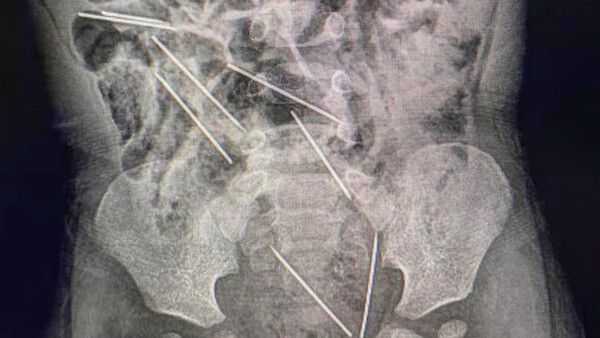

Diario HOY | Niño de 2 años tragó ocho agujas hipodérmicas: médicos logran salvarlo

La madre del menor presume que su hijo ingirió las agujas mientras estaba jugando en una finca. ...[Leer más]